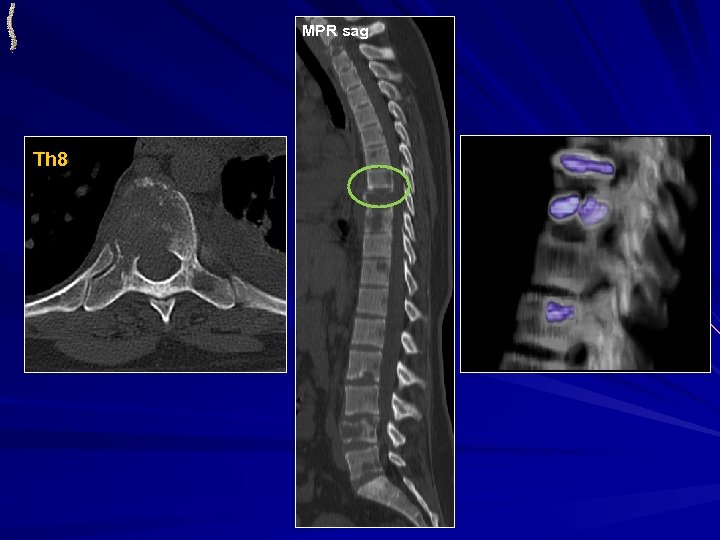

МИЕЛОМНАЯ БОЛЕЗНЬ • ЧАСТО МАНИФЕСТИРУЕТ ПАТОЛОГИЧЕСКИМИ ПЕРЕЛОМАМИ • ТРИ ФОРМЫ: ОЧАГОВО-ДЕСТРУКТИВНАЯ, ДИФФУЗНОПОРОТИЧЕСКАЯ И СКЛЕРОТИЧЕСКАЯ КТ: КТ-проявления зависят от формы миеломной болезни. Множественность поражения МРТ: Множественные достаточно однородные солидные очаги различных размеров Может быть внекостный компонент

МИЕЛОМНАЯ БОЛЕЗНЬ Th 8 MPR sag MPR cor Th 12